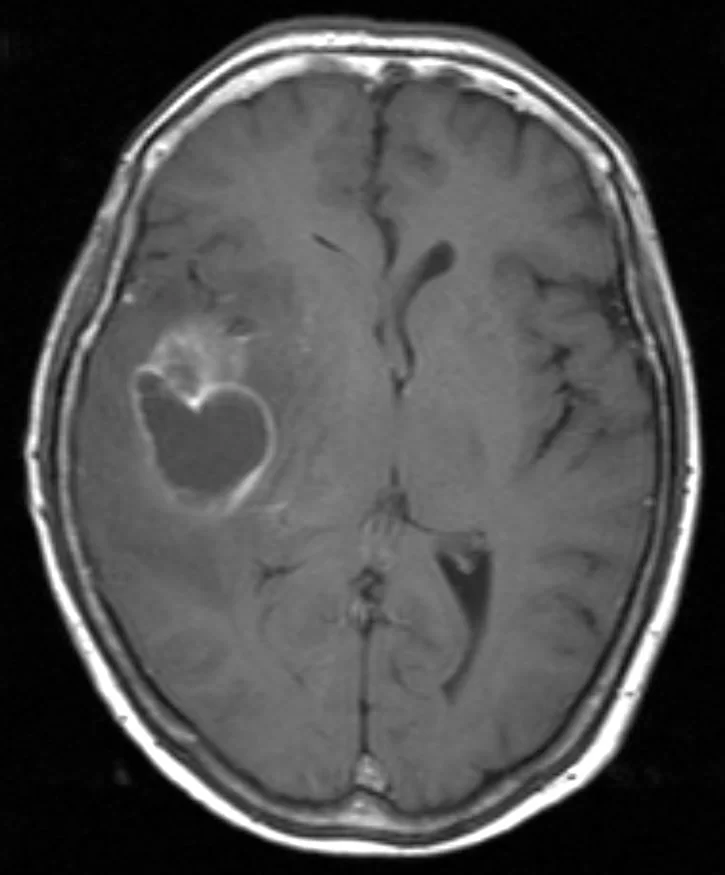

Η μαγνητική τομογραφία ανέδειξε ευμεγέθη χωροκατακτητική εξεργασία δεξιά κροταφικά με σημαντικό περιεστιακό οίδημα, ύποπτη για κακόηθες γλοίωμα.

Διενεργήθη δεξιά κροταφική κρανιοτομία και πλήρης εξαίρεση της βλάβης με τη βοήθεια νευροπλοήγησης, διεγχειρητικού υπερήχου αλλά κυρίως με τη χρήση 5-ALA ανοσοφθορισμού.

Η μετεγχειρητική μαγνητική τομογραφία εγκεφάλου (substraction sequences) δείχνει πλήρη αφαίρεση της βλάβης. Η ιστολογική εξέταση ανέδειξε γλοιοβλάστωμα (IDH1/2 mutant, MGMT neg).